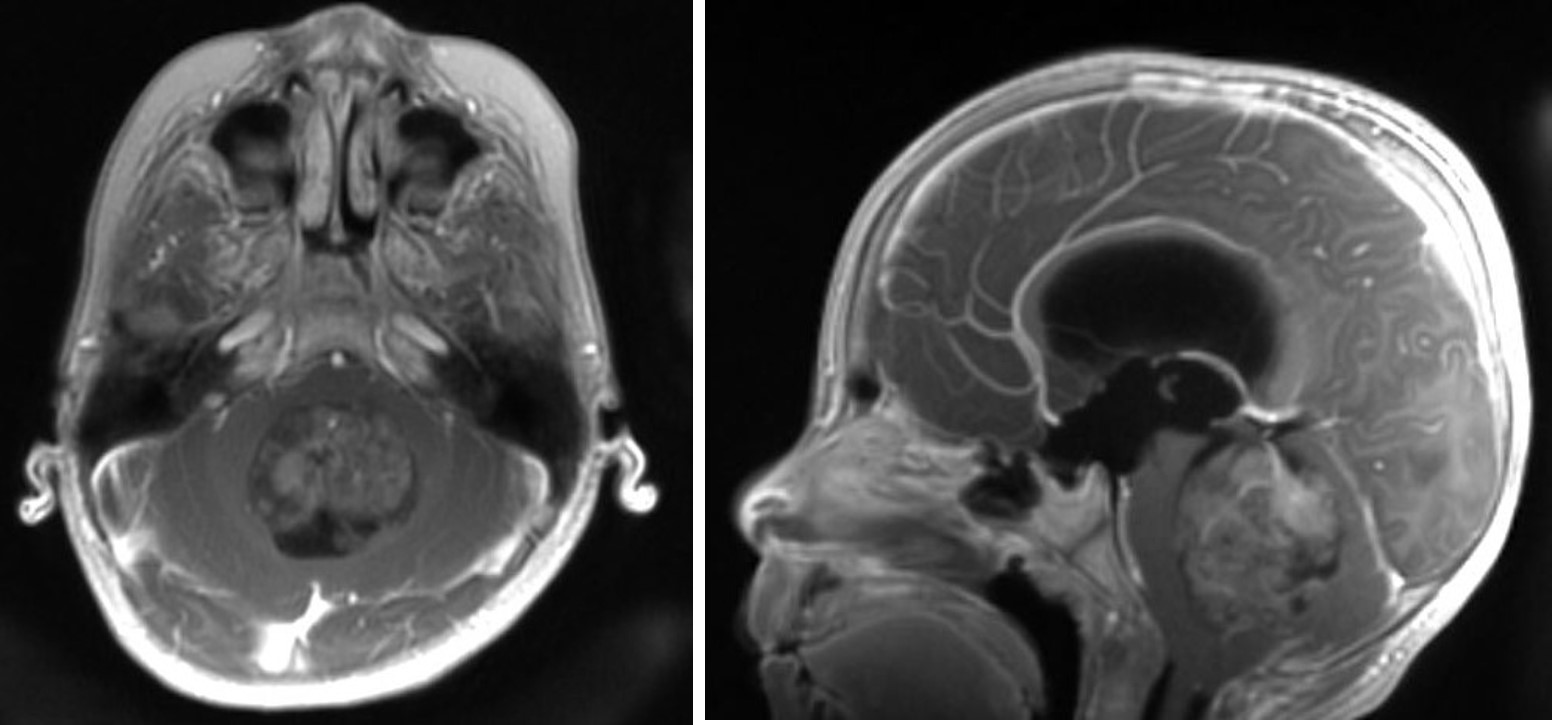

小脳の腫瘍が大きくなることにより第四脳室という脳脊髄液の循環経路を狭くすることから急速に頭に脳脊髄液の溜まる水頭症と呼ばれる状態(頭痛、嘔吐)で発見される場合もあります。MRIで小脳虫部から発生した腫瘍であれば髄芽腫が疑われます。

髄芽腫のMRI